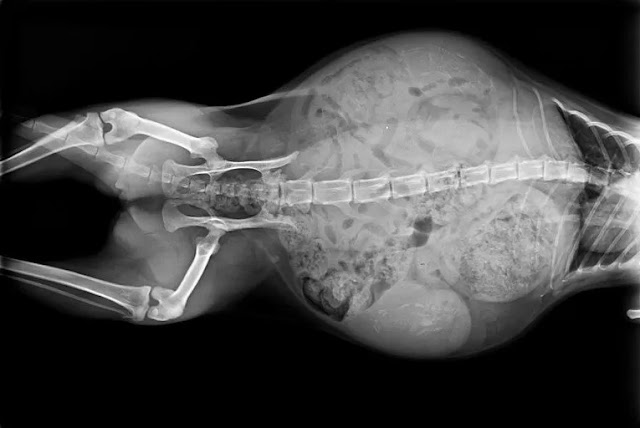

Engorged Stomach

It is not until fairly late in your cats pregnancy that their stomach will become noticeably larger. As the kittens grow in the womb your cats belly will grow and expand, however it is not until around the fifth week of your cat’s pregnancy that the cats belly will drop downwards giving your cat an obviously distended stomach.

In some cats it may be harder to tell if your cat has a particularly swollen stomach, it can be hard to tell if your cat has a lot of fluffy hair which may cover their stomach, they are quite fat cats, they have had a litter of kittens previously (as this can cause stretching if the stomach so that it will naturally drop down more), if they are just carrying one kitten their stomach will be significantly less distended than if they are carrying a large litter.